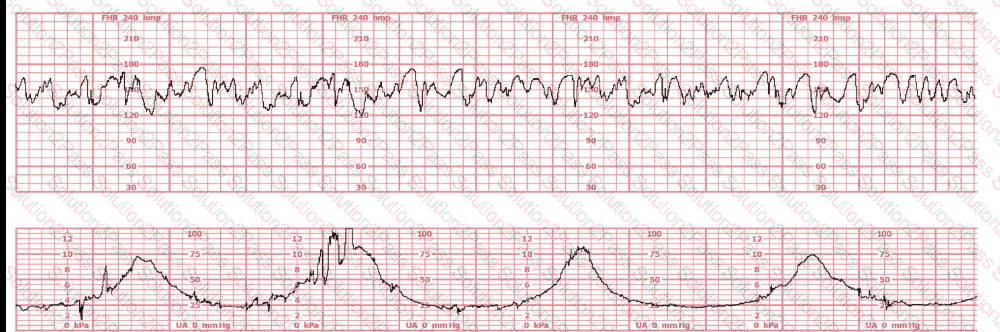

This fetal heart rate tracing is obtained upon the woman's admission to labor and delivery. This tracing is most reflective of:

The baseline fetal heart rate in this tracing is: